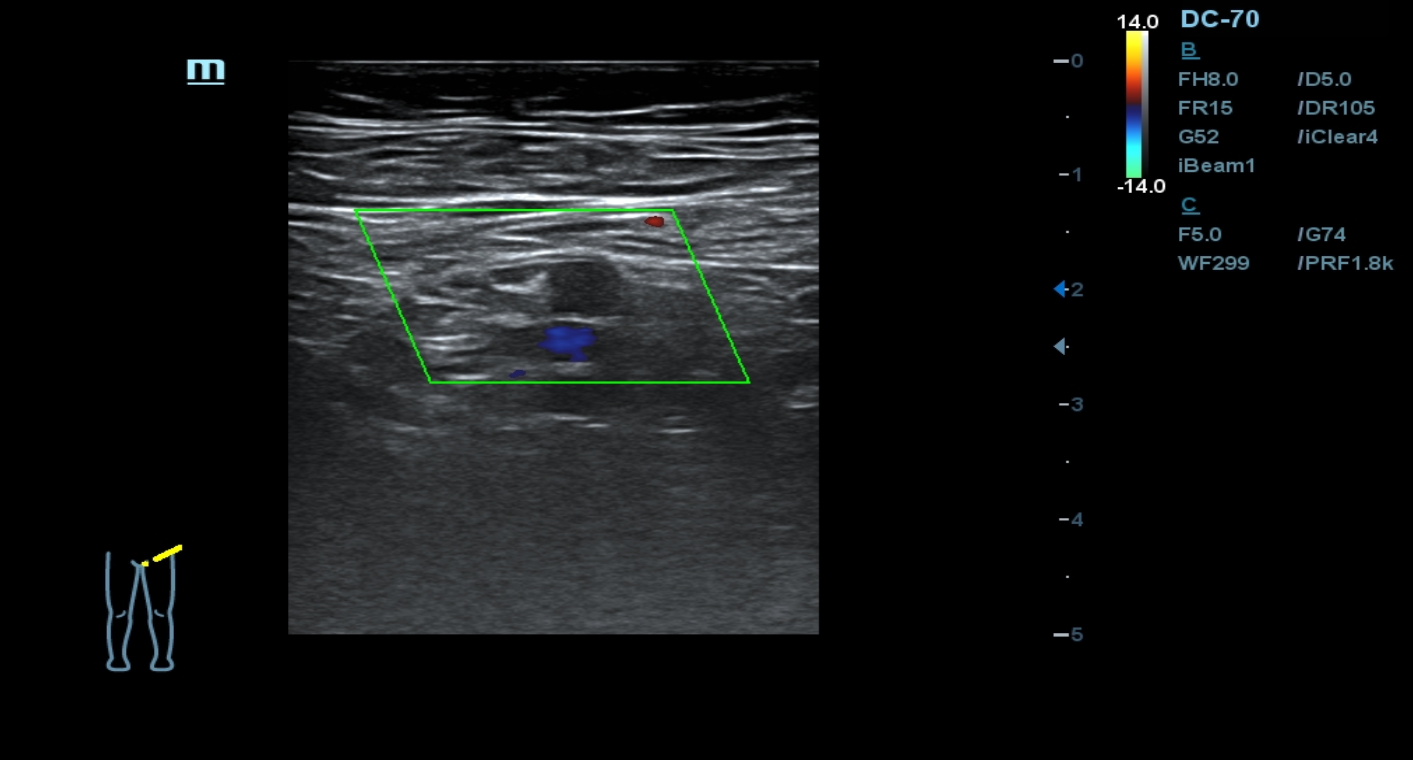

Ante los antecedentes patológicos de nuestro paciente, junto con los hallazgos relevantes de la anamnesis y exploración física decidimos realizar una ecografía clínica de miembros inferiores. En la arteria femoral común el flujo está presente. En la arteria femoral superficial se observa una obstrucción total. Así mismo, en un corte longitudinal de la arteria poplítea y tibial observamos una obstrucción total.